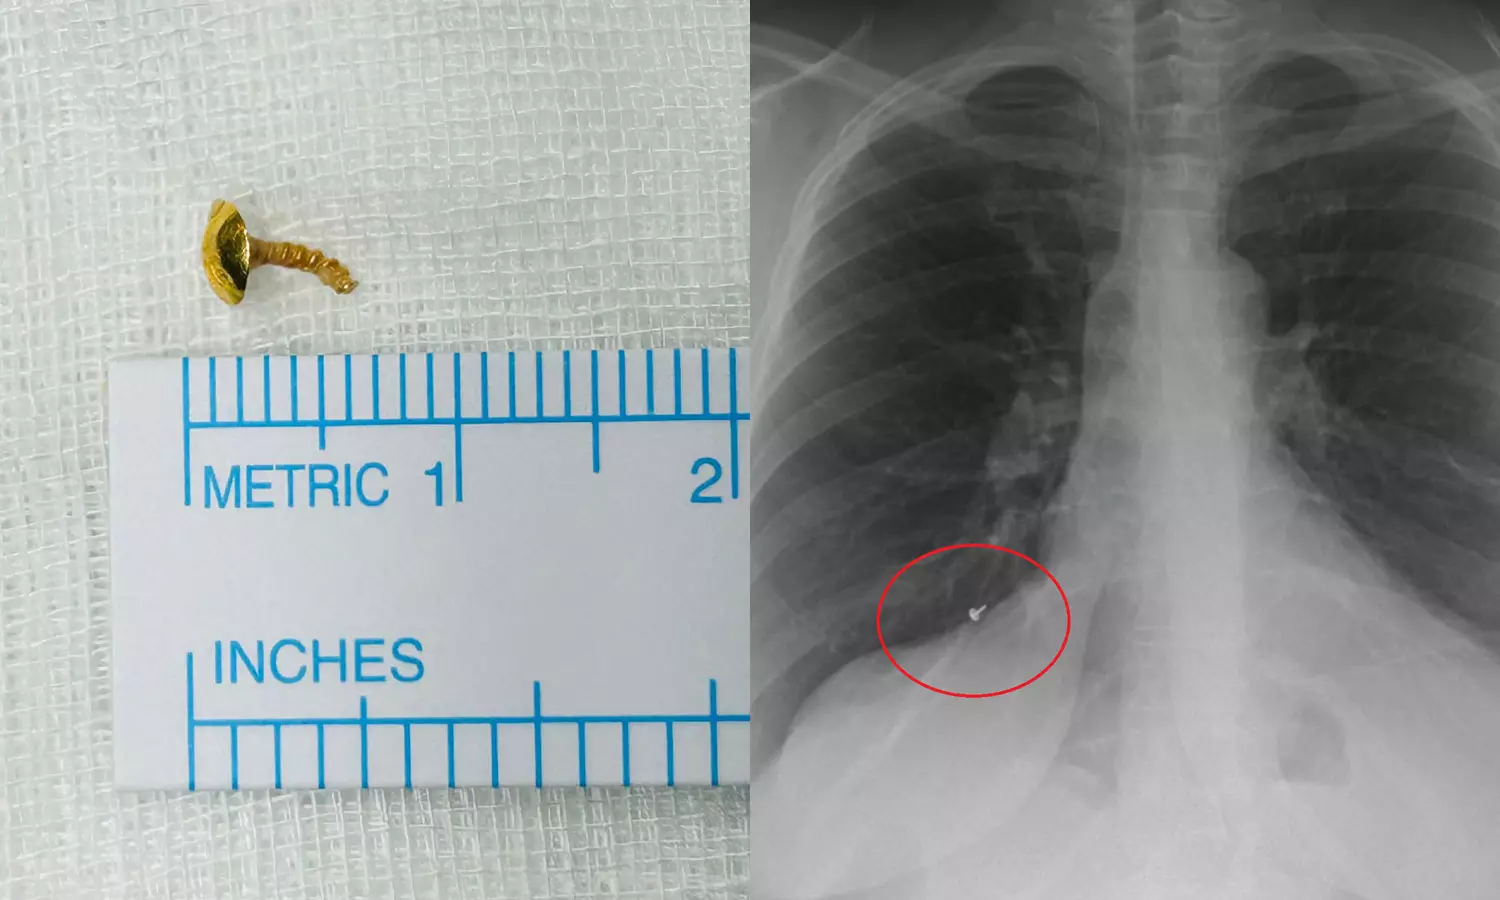

കൊച്ചി: വീട്ടമ്മയുടെ ശ്വാസകോശത്തിൽ നിന്ന് ഒരു സെന്റിമീറ്റർ നീളത്തിലുള്ള മൂക്കുത്തിയുടെ ഭാഗം പുറത്തെടുത്തു. കൊല്ലം ശാസ്താംകോട്ട സ്വദേശിനിയായ 44കാരിയുടെ ശ്വാസകോശത്തിൽ നിന്നാണ് മൂക്കുത്തിയുടെ ചങ്കിരി പുറത്തെടുത്തത്. കൊച്ചി അമൃത ആശുപത്രിയിലെ ഡോക്ടർമാരാണ് ശസ്ത്രക്രിയ കൂടാതെ മൂക്കുത്തിയുടെ ഭാഗം പുറത്തെടുത്തത്.

ഒടുവിൽ കഴിഞ്ഞയാഴ്ച കൊല്ലത്തെ സ്വകാര്യ ആശുപത്രിയിൽ ശസ്ത്രക്രിയയ്ക്ക് വിധേയയായപ്പോൾ നടത്തിയ സ്കാനിങ്ങിലാണ് ശ്വാസകോശത്തിൽ എന്തോ തറഞ്ഞിരിക്കുന്നതായി കണ്ടെത്തിയത്. തുടർന്ന് വിദഗ്ധ ചികിത്സയ്ക്കായി കൊച്ചിയിലെ ആശുപത്രിയിലെത്തുകയായിരുന്നു. ഡോ.ടിങ്കു ജോസഫിന്റെ നേതൃത്വത്തിൽ നടത്തിയ പരിശോധനയിൽ ഇത് മൂക്കുത്തിയുടെ ഭാഗമാണെന്ന് കണ്ടെത്തുകയും റിജിഡ് ബ്രോങ്കോസ്കോപിയിലൂടെ പുറത്തെടുക്കുകയുമായിരുന്നു.

ഒരു ദിവസത്തെ വിശ്രമത്തിനു ശേഷം യുവതി കഴിഞ്ഞദിവസം ആശുപത്രി വിട്ടു. ഉറക്കത്തിനിടെ ഊരിപ്പോയ മൂക്കുത്തിയുടെ ഭാഗം മൂക്കിനുള്ളിലൂടെ വായിലെത്തി ശ്വാസകോശത്തിലേക്ക് പോയതാവാമെന്നാണ് കരുതുന്നത്. ഈ കാലയളവിൽ ശ്വാസതടസവും മറ്റു ബുദ്ധിമുട്ടുകളും നേരിട്ടതിനെ തുടർന്ന് വീട്ടമ്മ ആസ്തമയ്ക്ക് ചികിത്സ തേടുകയും ചെയ്തിരുന്നു.